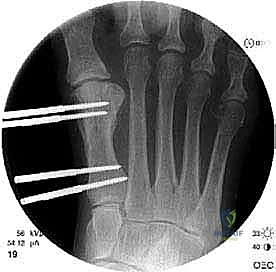

الخطوة الخامسة: التثبيت الداخلي القوي (Internal Fixation)

لضمان التئام العظم في وضعه الجديد والطويل، يجب تثبيته بقوة شديدة. يستخدم الدكتور هطيف أحدث الشرائح المعدنية التيتانيوم ذات الزاوية الثابتة (Locking Plates) والمسامير الدقيقة. هذا التثبيت القوي يمنع أي حركة بين العظام ويسمح ببدء العلاج الطبيعي في وقت مبكر.

الخطوة الثالثة: قص العظم (Osteotomy)

باستخدام منشار جراحي ميكروسكوبي دقيق، يقوم الدكتور هطيف بقص عظم مشط القدم. تعتمد زاوية وشكل القص (مثل القص المائل أو القص على شكل حرف Z) على مقدار الإطالة المطلوبة وشكل العظم المتبقي من الجراحة السابقة.